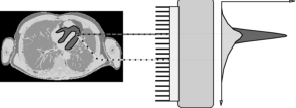

If we plot all the measurements in a histogram, we will see the distribution. Usually the distribution is approximately Gaussian, and can be characterized by its standard deviation σ. Often one specifies the full width at half maximum (FWHM) instead (Figure 3). It is easy to show that for a Gaussian, the FWHM . This leads to a useful rule of thumb: any detail smaller than the FWHM is lost during the measurement.

Figure 3:The full width at half max of a probability distribution

Position resolution of a scintillation detector has a FWHM of 3 to 4 mm. Energy resolution is about 10% FWHM at 140 keV in NaI(Tl) cameras, about 12% FWHM at 511 keV in BGO PET-systems, and about 10% FWHM in LSO and LYSO PET-systems.